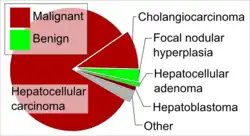

Cholangiocarcinoma, also known as bile duct cancer, is a type of cancer that forms in the bile ducts.[2] Symptoms of cholangiocarcinoma may include abdominal pain, yellowish skin, weight loss, generalized itching, and fever.[1] Light colored stool or dark urine may also occur.[4] Other biliary tract cancers include gallbladder cancer and cancer of the ampulla of Vater.[7]

Cholangiocarcinoma is rare in the Western world, with estimates of it occurring in 0.5–2 people per 100,000 per year.[1][6] Rates are higher in Southeast Asia where liver flukes are common.[5] Rates in parts of Thailand are 60 per 100,000 per year.[5] It typically occurs in people in their 70s, and in the 40s for those with primary sclerosing cholangitis.[3] Rates of cholangiocarcinoma within the liver in the Western world have increased.[6]

Cholangiocarcinoma is a relatively rare form of cancer; each year, approximately 2,000 to 3,000 new cases are diagnosed in the United States, translating into an annual incidence of 1–2 cases per 100,000 people.[106] Autopsy series have reported a prevalence of 0.01% to 0.46%.[83][107] There is a higher prevalence of cholangiocarcinoma in Asia, which has been attributed to endemic chronic parasitic infestation. The incidence of cholangiocarcinoma increases with age, and the disease is slightly more common in men than in women (possibly due to the higher rate of primary sclerosing cholangitis, a major risk factor, in men).[48] The prevalence of cholangiocarcinoma in people with primary sclerosing cholangitis may be as high as 30%, based on autopsy studies.[15]

Multiple studies have documented a steady increase in the incidence of intrahepatic cholangiocarcinoma; increases have been seen in North America, Europe, Asia, and Australia.[108] The reasons for the increasing occurrence of cholangiocarcinoma are unclear; improved diagnostic methods may be partially responsible, but the prevalence of potential risk factors for cholangiocarcinoma, such as HIV infection, has also been increasing during this time frame.[27]